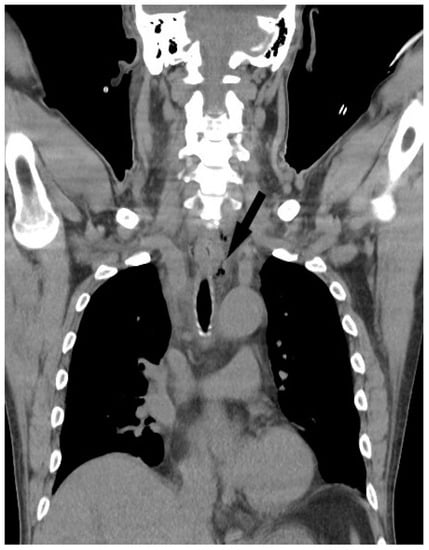

- Scaglione, M.; Pinto, A.; Giovine, S.; Di-Nuzzo, L.; Giuliano, V.; Romano, L. CT features of descending necrotizing mediastinitis--a pictorial essay. Emerg. Radiol. 2007, 14, 77–81. [Google Scholar] [CrossRef]